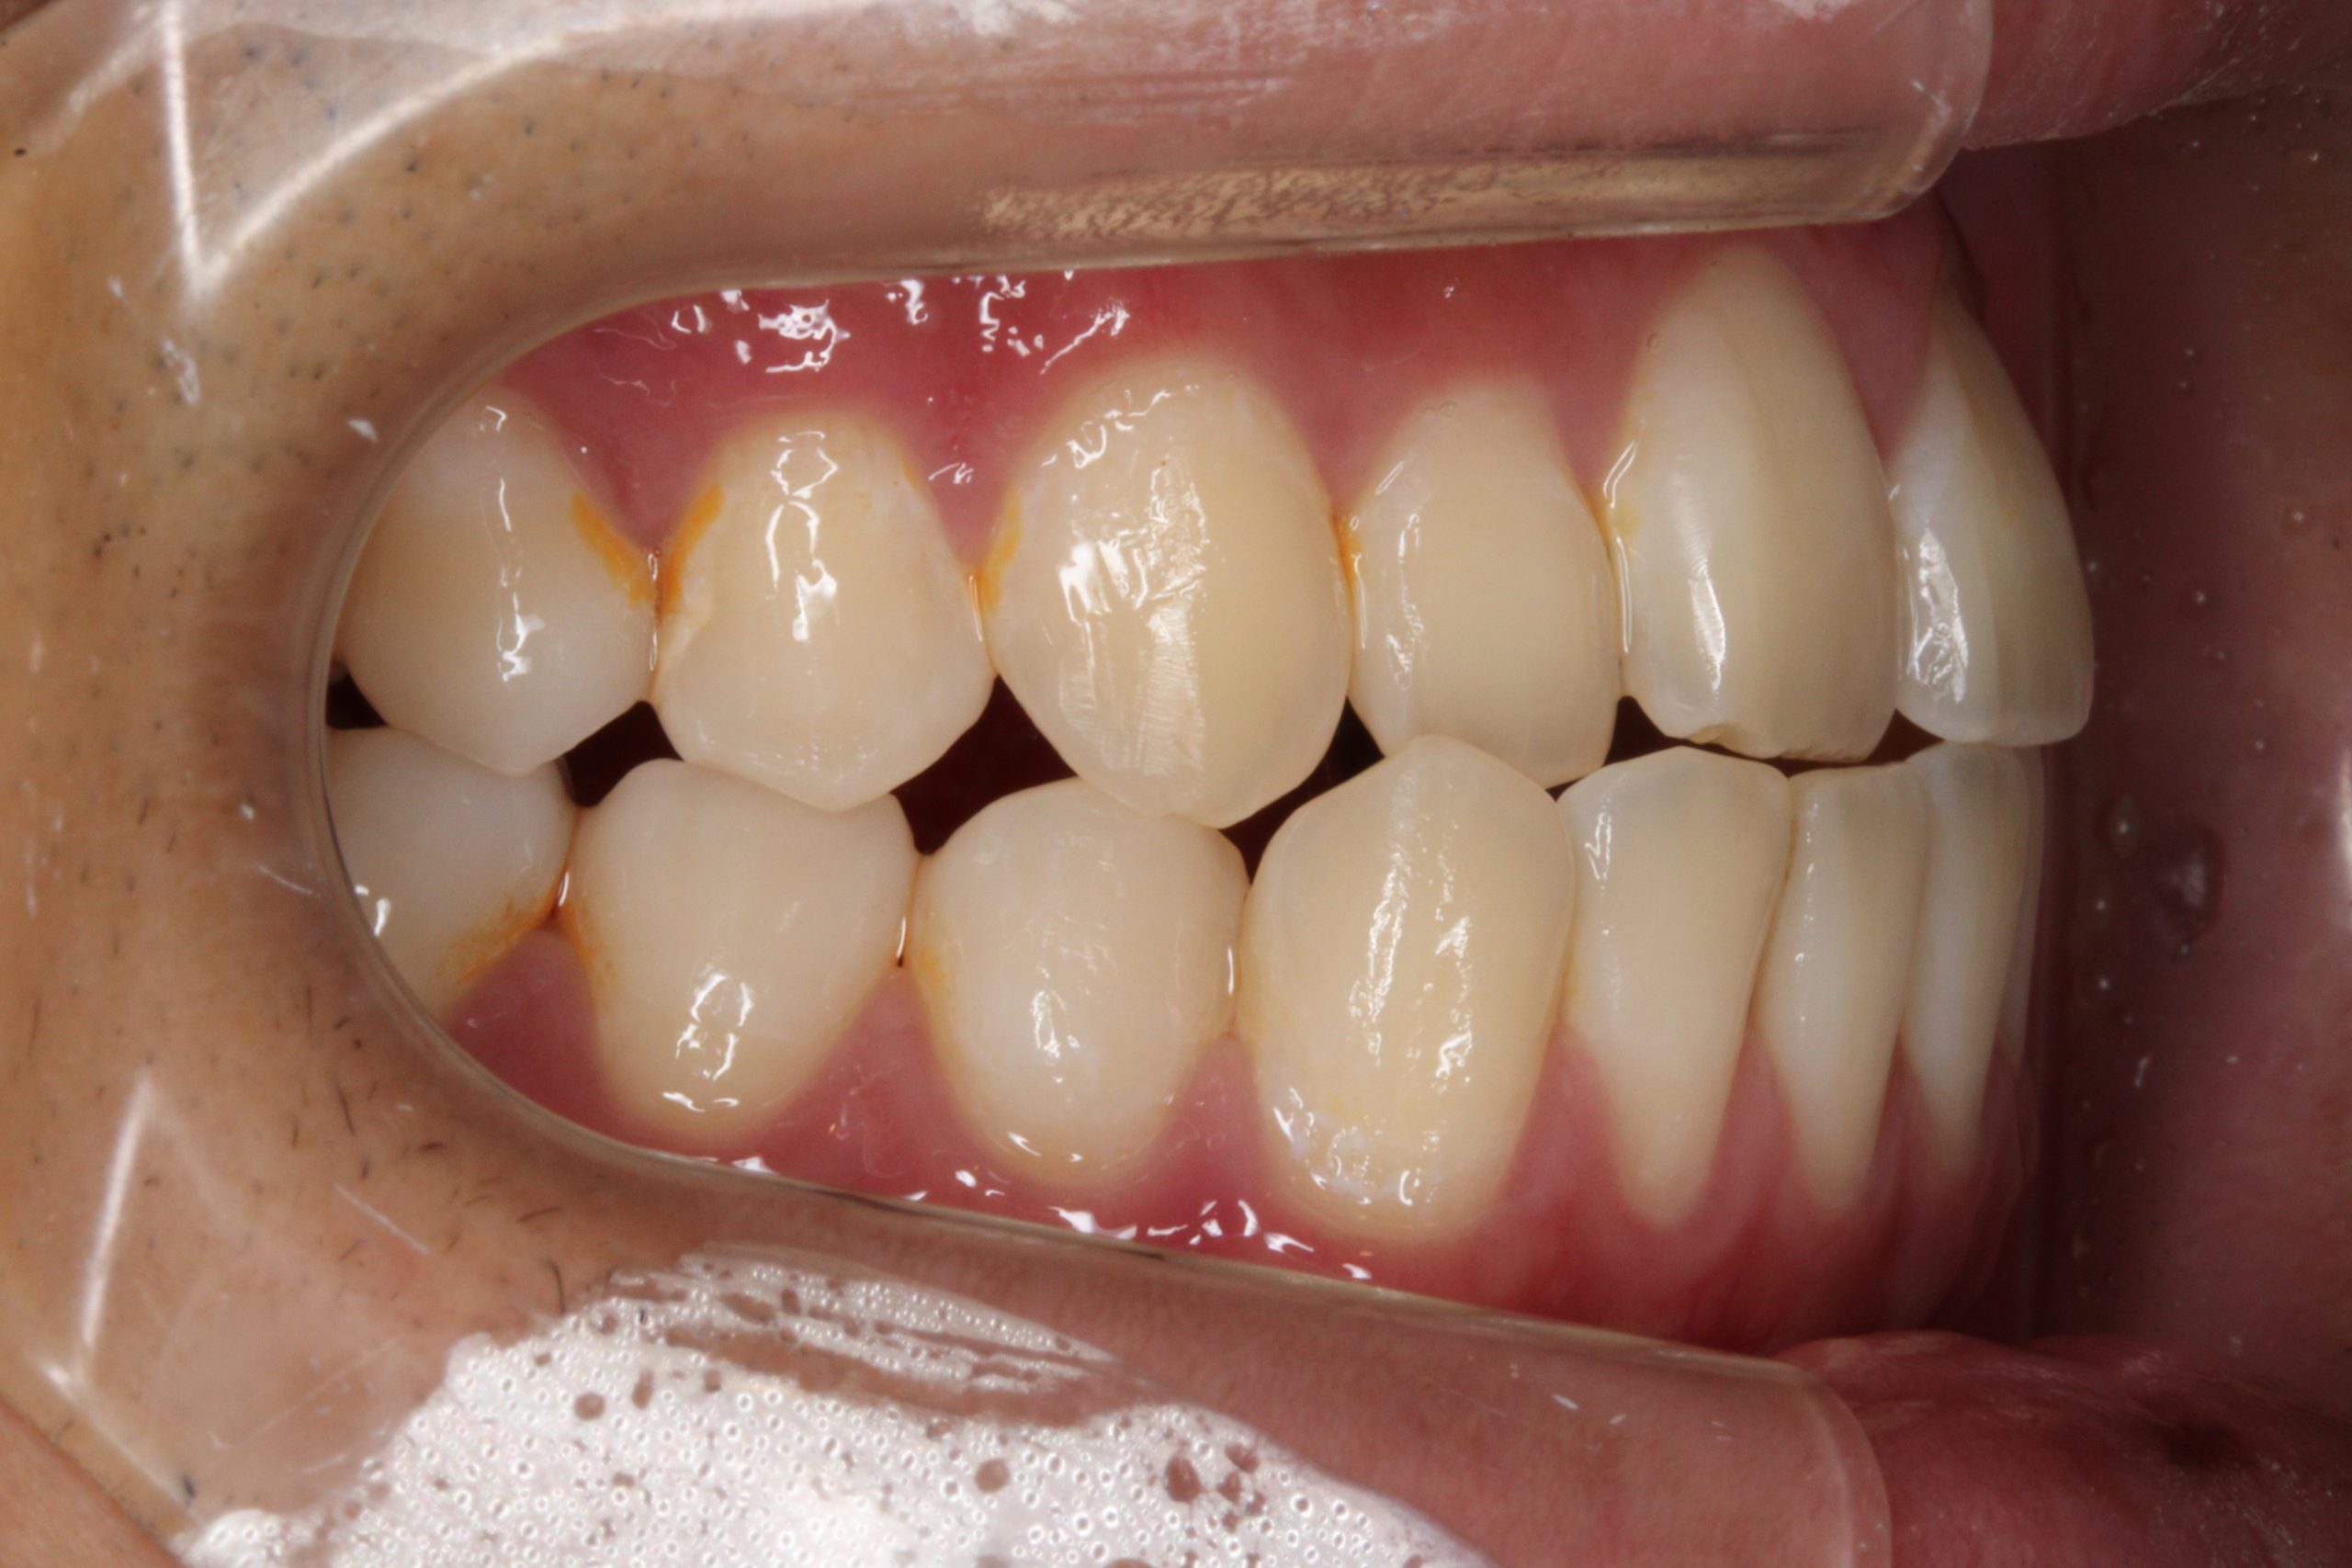

下の歯が出ている ・噛んだ時に、下の歯と上の歯がかみ合わない

| 主訴 | 下の歯が出ている ・かんだ時に、下の歯と上の歯がかみ合わない |

Before